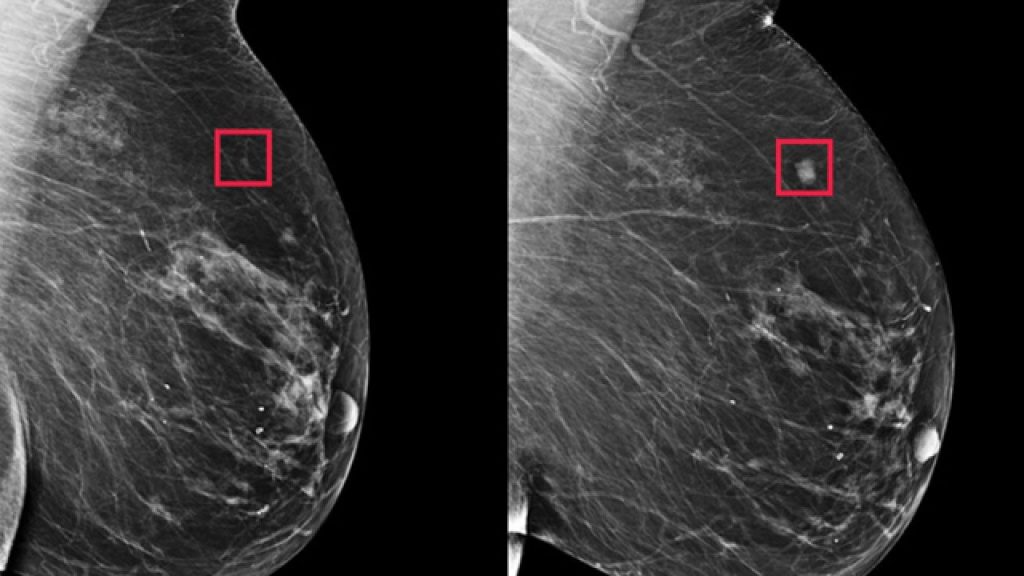

Představte si to: tisíce mamografů , desítky tisíc životů, miliony mikroskopických signálů v tkáni prsu, které ani zkušený lékař neuvidí pod sebepřesnějším přístrojem – a algoritmus je přečte během jediné vteřiny. Jako kdyby rozuměl tajnému textu ukrytému hluboko v lidském těle.

A najednou se ukáže, že model vyvinutý na MIT dokáže ženě říct, že má vysoké riziko rakoviny pět let předtím, než se objeví jakýkoli příznak. Dřív, než přijde bolest, zatvrdnutí, změna struktury, než se ozve jediný varovný tón. Žijeme v době, kdy algoritmus dokáže varovat před něčím, co lidský lékař ještě vůbec nevidí – a to mění úplně všechno: náš vztah k medicíně, k vlastnímu tělu, k tomu, jak vnímáme strach i naději .

A přesto… když existuje šance dozvědět se pravdu včas, existuje i šance přežít. Zasáhnout, připravit se, ochránit. Umělá inteligence se tak nestává věštcem, ale lupou pro část reality, která byla dosud skrytá.

Není to magie. Je to nová vrstva zraku.